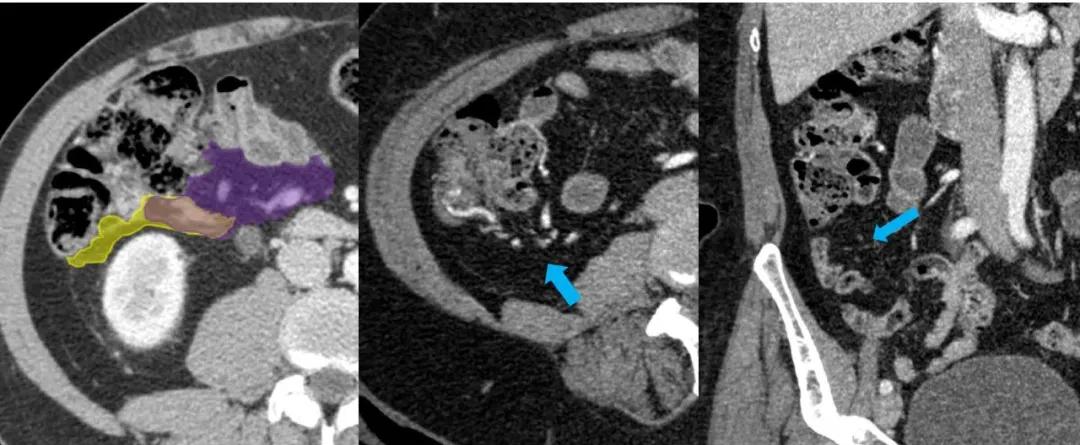

回盲部:小肠系膜(紫色)和右侧结肠系膜(黄色)与回结肠血管(蓝箭头)的汇合处。